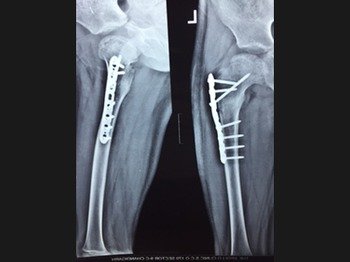

Dr. M.S. Narula is a leading trauma orthopaedic surgeon who offers minimally invasive and small incision techniques to provide state of the art care to his patients. Whether you require a second opinion or emergency treatment, he offers specialized fracture management for simple, complex and neglected fracture.

Orthopedic trauma cases are particularly difficult to treat, but with the right skill, technique, and experience, Dr. M.S. Narula provides excellent care to treat the trauma and progress towards complete recovery & minimal or no disability.

These surgeries are the most difficult and challenging to treat. Dr Narula uses 3 generation techniques with special implants and Grafts to treat such complicated cases.